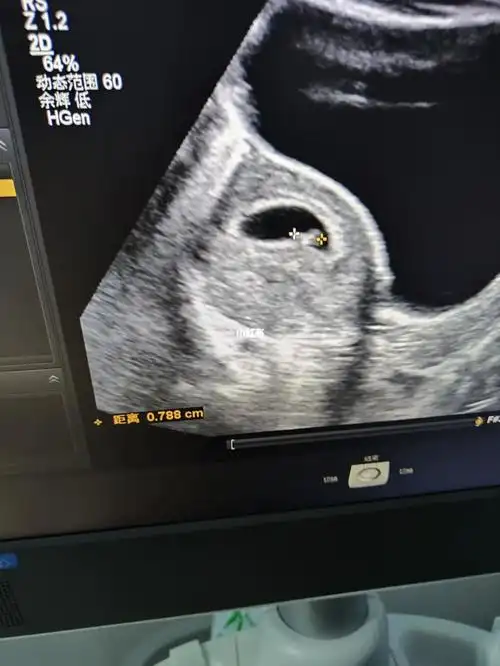

有胎心胎芽了